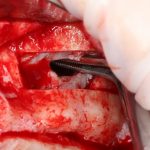

Я зафиксировал костный блок практически без адаптации на несколько винтов. Обрати внимание, что винты находятся в зоне, где не планируется установка имплантатов. Фиксация должна быть надежной, поскольку мне еще предстояла подготовка лунок для имплантатов. Трех винтов для этого вполне достаточно.

Дальнейшая адаптация костного блока свелась к сглаживанию острых краев. После чего я приступил к подготовке лунок и установке имплантатов.

Установка имплантатов.

Напомню, что для этой работы я выбрал субкрестальные имплантаты Ankylos C/X. Они прекрасно сочетаются с любым методом остеопластики.

Я не планирую установку супраструктур или коронок, поэтому на уровень первичной стабильности можно положить болт. Даже наоборот — чем меньше крутящий момент при установке, тем лучше. Для имплантатов Ankylos и подобных им, это особенно важно. В общем, момент силы при установке — не более 10-15 Нсм.

Ремарка: имплантаты с предустановленными имплантодержателями хороши тем, что с ними легко контролировать позиционирование имплантатов. В случае с Ankylos С/Х - еще и крутящий момент. Имплантодержатель должен отсоединяться от имплантата с легким щелчком. Если его клинит, и тебе приходится прикладывать для этого усилия, то ты, однозначно, превысил момент силы во время установки имплантата. Следовательно, жди проблем.